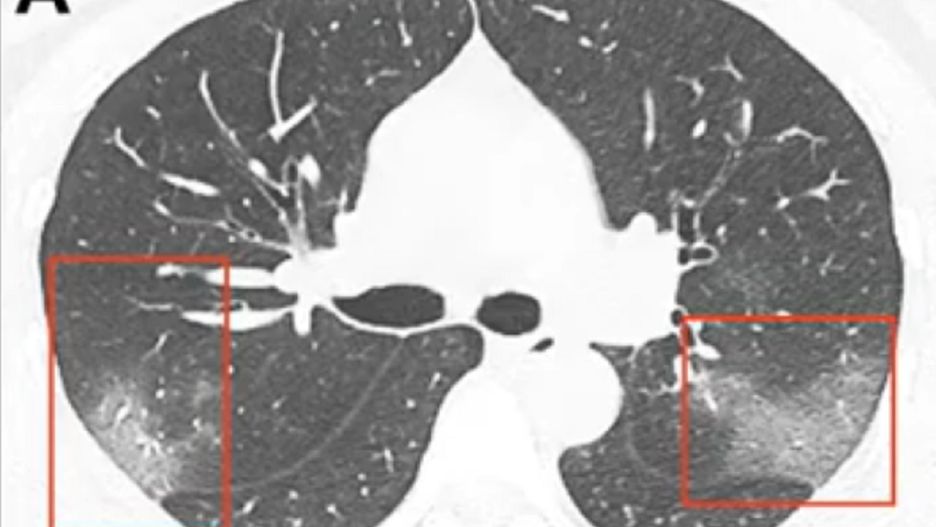

Badacze z uniwersyteckiego szpitala w chińskim Lanzhou opublikowali dwie fotografie, na których możemy zaobserwować wpływ śmiertelnie niebezpiecznego koronawirusa na płuca. Zdjęcia zamieszczone w czasopiśmie naukowym "Radiology" zostały uzyskane za pomocą tomografii komputerowej 33-letniej pacjentki. Na pierwszym z nich widać dwa zamglone miejsca, na drugim - wykonanym trzy dni później, jak dotknięty obszar się powiększa.

Paras Lakhani, radiolog z Thomas Jefferson University, analizując zdjęcie udostępnione przez lekarzy z Lanzhou zwraca szczegółną uwagę na "obecność płynu w przestrzeniach płucnych".

Kobieta, która pracowała wcześniej w mieście Wuhan, zgłosiła się do szpitala w Lanzhou po pięciu dniach zmagania się z gorączką i kaszlem. Podczas hospitalizacji temperatura jej ciała wzrosła do 39 stopni Celsjusza, a tomografia komputerowa wykazała spore zmętnienie w obu płucach. Pacjentka została poddana natychmiastowemu leczeniu, w trakcie którego lekarze zdecydowali się na inhalację interferonem.